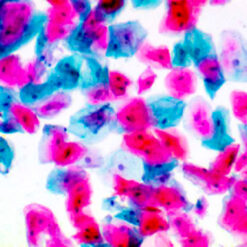

This kit stains strongly sulfated mucosubstances. Strongly sulfated mucosub-stances stain blue in paraffin tissue sections, while the nuclei stain pink to red and the cytoplasm and background stain pale pink.